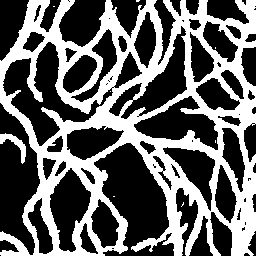

Semantic segmentation of blood vessels is an important task in medical image analysis, but its progress is often hindered by the scarcity of large annotated datasets and the poor generalization of models across different imaging modalities. A key aspect is the tendency of Convolutional Neural Networks (CNNs) to learn texture-based features, which limits their performance when applied to new domains with different visual characteristics. We hypothesize that leveraging geometric priors of vessel shapes, such as their tubular and branching nature, can lead to more robust and data-efficient models. To investigate this, we introduce VessShape, a methodology for generating large-scale 2D synthetic datasets designed to instill a shape bias in segmentation models. VessShape images contain procedurally generated tubular geometries combined with a wide variety of foreground and background textures, encouraging models to learn shape cues rather than textures. We demonstrate that a model pre-trained on VessShape images achieves strong few-shot segmentation performance on two real-world datasets from different domains, requiring only four to ten samples for fine-tuning. Furthermore, the model exhibits notable zero-shot capabilities, effectively segmenting vessels in unseen domains without any target-specific training. Our results indicate that pre-training with a strong shape bias can be an effective strategy to overcome data scarcity and improve model generalization in blood vessel segmentation.